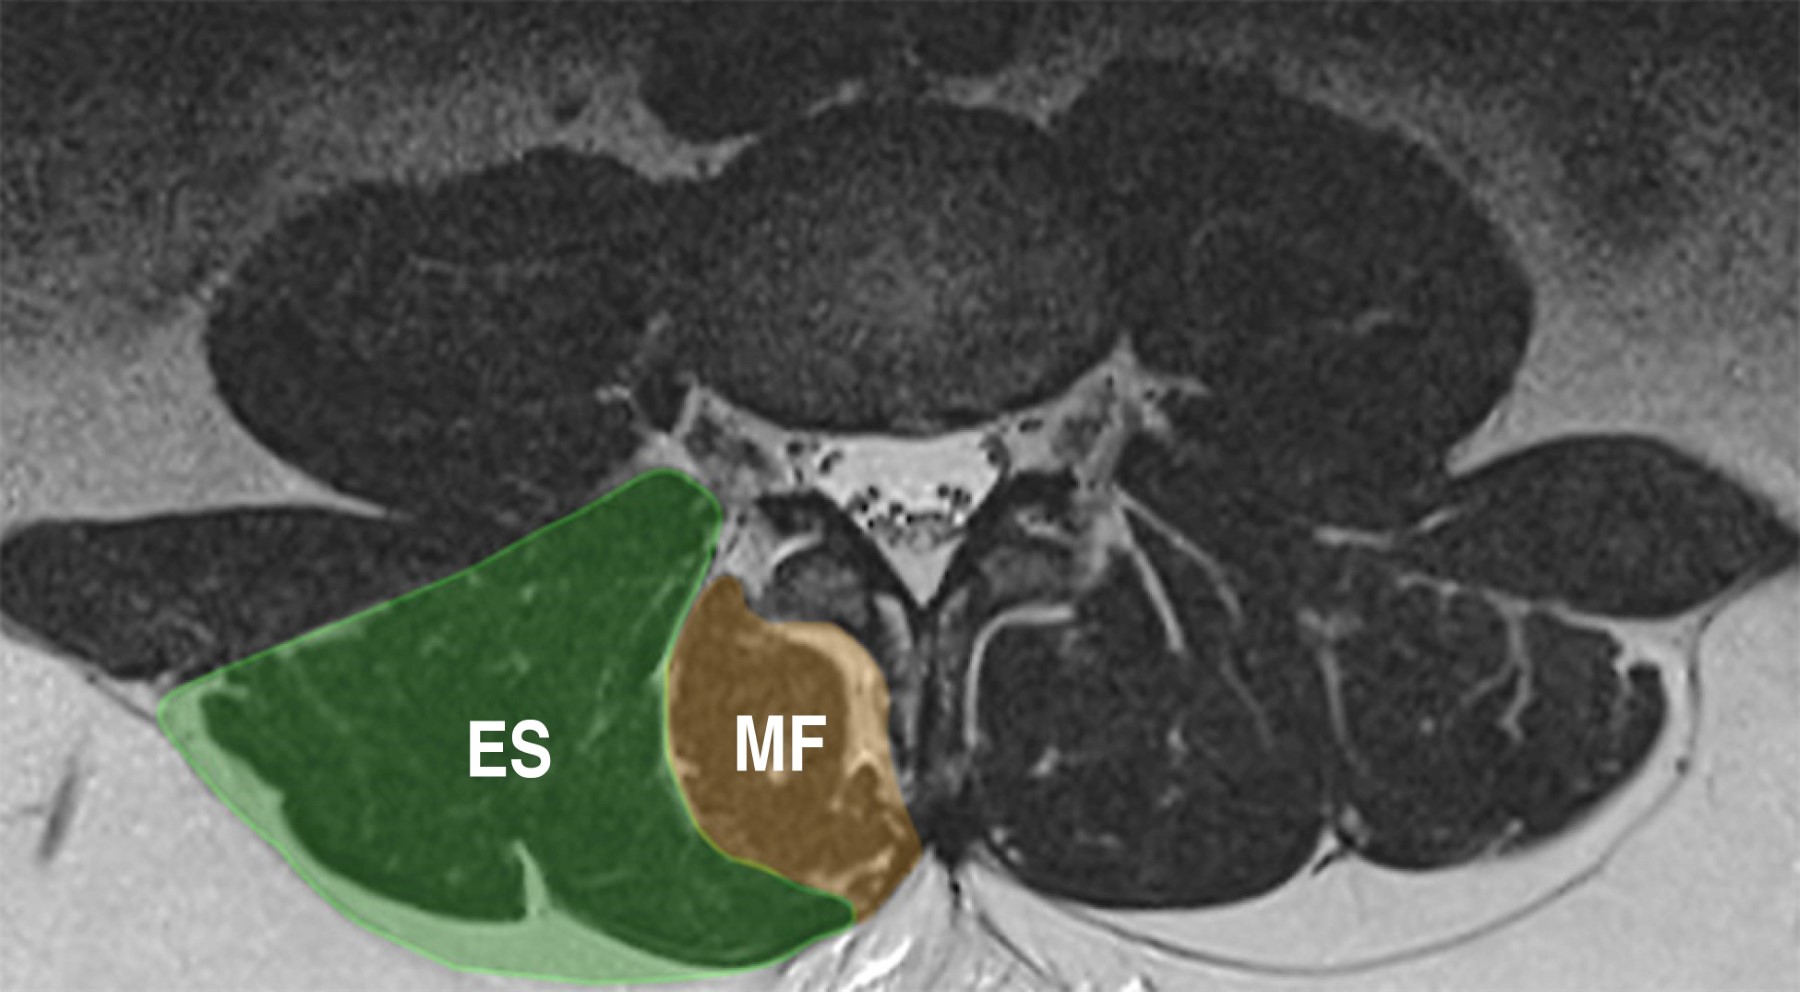

El dolor en la ELD es un fenómeno complejo y multifactorial, caracterizado por la interacción de múltiples estructuras anatómicas involucradas en la generación y mantenimiento de este síntoma; entre éstas, se encuentran los músculos multífidos y erector espinal, que conforman la musculatura paravertebral posterior (MPP) (Figura 1) y que juegan un papel importante en el mantenimiento del balance global de la columna lumbar.4 Estos músculos antagonizan a los flexores espinales con el objetivo de mantener una posición neutra, además de contribuir con la estabilización segmentaria lumbar.5 Los cambios degenerativos de la musculatura paravertebral se caracterizan por la disminución del tamaño muscular (atrofia) y la sustitución de fibras musculares por depósitos de grasa (infiltración).6 Estos cambios son frecuentes en pacientes con ELD y aunque se han relacionado con la edad, existen múltiples factores que pueden contribuir con su desarrollo, como: el estado nutricional, la obesidad, el grado de actividad física o el género.7,8 Cuando no se obtienen los resultados deseados con el manejo conservador en pacientes con ELD, se considera la opción del tratamiento quirúrgico. La técnica tradicional generalmente implica abordajes sobre la línea media posterior de la columna lumbar, con disección muscular subperióstica; dependiendo de las características clínicas y anatomofisiológicas del paciente, ésta puede complementarse con procedimientos de fusión intersomática e instrumentación posterior para proporcionar estabilidad adicional a la columna. No obstante, es importante señalar que este enfoque quirúrgico puede ocasionar lesiones iatrogénicas en la musculatura paraespinal. Como resultado de la lesión a un músculo atrófico, se ha documentado el desarrollo de dolor lumbar postoperatorio y la posibilidad de inestabilidad segmentaria, lo cual puede afectar negativamente la recuperación del paciente y su calidad de vida.4,5,7,9 Diversos estudios han intentado establecer una relación entre la atrofia muscular y eventos adversos postoperatorios.10-14 No obstante, se han encontrado discrepancias en los resultados obtenidos. Este desacuerdo puede atribuirse, en parte, a la falta de uniformidad en las definiciones y métodos diagnósticos utilizados.12,15,16

Se delimitó el área de sección transversal (CSA) de los músculos erector espinal y multífidos derechos e izquierdos, que conforman los MPP, utilizando un cursor gráfico para trazar un contorno alrededor de la fascia muscular que los rodea. Es decir, el CSA se identificó desde el límite dorsal del músculo cuadrado lumbar, continuando a lo largo de la superficie posterior de la faceta articular, lámina vertebral y la apófisis espinosa. Esto permitió una definición clara del límite anatómico muscular a estudiar. De la misma forma, se determinó el CSA del cuerpo vertebral de L3, utilizando como referencia su plataforma terminal inferior, excluyendo la consideración de osteofitos y tejido del disco intervertebral (Figura 2).